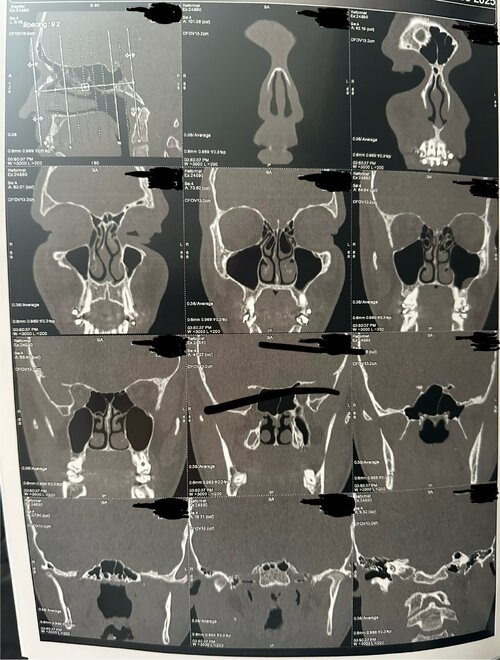

The CT scan provides a detailed view of the upper airway, nasal passages, and palate from multiple angles (axial, coronal, and sagittal). Based on the visible structures, several key anatomical features can be observed that relate to breathing efficiency, oral posture, and orthodontic development.

2. Nasal Airway

The nasal passages appear structurally clear, with no major obstruction or sinus blockage. The nasal septum seems mostly straight, though there may be a minor deviation toward one side in the lower portion. The inferior turbinates (soft tissue ridges inside the nasal cavity) show slight asymmetry, which is common and can contribute to uneven airflow between sides.

Because the palate forms the floor of the nasal cavity, a narrow palate typically reduces nasal base width. This can result in less efficient airflow through the nose, encouraging mouth breathing or snoring, especially during sleep. Expansion of the palate — if possible — can indirectly increase nasal volume, improving airflow and breathing comfort.

The CT scan provides a detailed view of the upper airway, nasal passages, and palate from multiple angles (axial, coronal, and sagittal). Based on the visible structures, several key anatomical features can be observed that relate to breathing efficiency, oral posture, and orthodontic development.

2. Nasal Airway

The nasal passages appear structurally clear, with no major obstruction or sinus blockage. The nasal septum seems mostly straight, though there may be a minor deviation toward one side in the lower portion. The inferior turbinates (soft tissue ridges inside the nasal cavity) show slight asymmetry, which is common and can contribute to uneven airflow between sides.

Because the palate forms the floor of the nasal cavity, a narrow palate typically reduces nasal base width. This can result in less efficient airflow through the nose, encouraging mouth breathing or snoring, especially during sleep. Expansion of the palate — if possible — can indirectly increase nasal volume, improving airflow and breathing comfort.